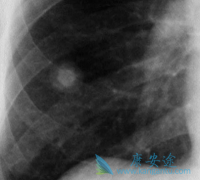

人们都治疗肺癌是比较难治的恶性疾病,主要是因为肺癌的易发性,一般来说,肺癌术后1~2年内病人都有复发的可能,多以人们应了解肺癌为何会复发,应如何做好准备。即使早期肺癌手术后也是极易复发的,这是因为肿瘤细胞是极为难以清除的,复发多半发生在手 ...

在所有的恶性肿瘤中,肺癌往往给人既熟悉又可怕的印象。说熟悉它,是因为不知从何时起,我们身边总会有人患有这种疾病;说它可怕,是因为肺癌的死亡率居所有恶性肿瘤之首!肺癌起病隐匿,通常早期肺癌无任何症状,而发现时,往往已经发生了侵袭转移。 转 ...

由于空气污染、吸烟等因素,肺癌的发病率逐年递增,且在世界范围内,肺癌为最危险的恶性肿瘤之一,其被称为癌中之癌王。据报道,绝大多数患者被确诊为肺癌时均以到了癌症中晚期,那么, 肺癌晚期有什么症状 ?肺癌晚期症状:气促,胸腔积液。发生区域性 ...

一般肺癌发现都比较晚,很多病人和家属都不敢信息,因为好好的一个人就被确诊为肺癌晚期了,实在难以接受,今天小编给大家讲下肺癌晚期症状,以及治疗。肺癌疼痛,声音嘶哑,面、颈部水肿,气促、胸腔积液等都是常见的 肺癌晚期症状 。   除了这些症状 ...